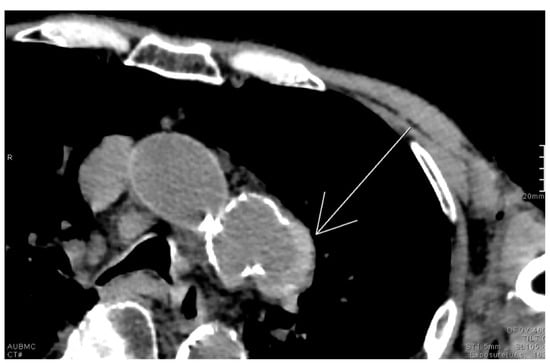

2.2. Earth-Heart Sign

- Clancy, D.J.; Lane, A.S.; Flynn, P.W.; Seppelt, I.M. Tension pneumomediastinum: A literal form of chest tightness. J. Intensive Care Soc. 2017, 18, 52–56. [Google Scholar] [CrossRef]

- Carillo, G.A.O.; Caballero, G.B.; Carretero, M.Á.C. The Earth-Heart sign: A new diagnostic finding in a patient with tension pneumomediastinum. Lancet 2014, 383, 486. [Google Scholar] [CrossRef]